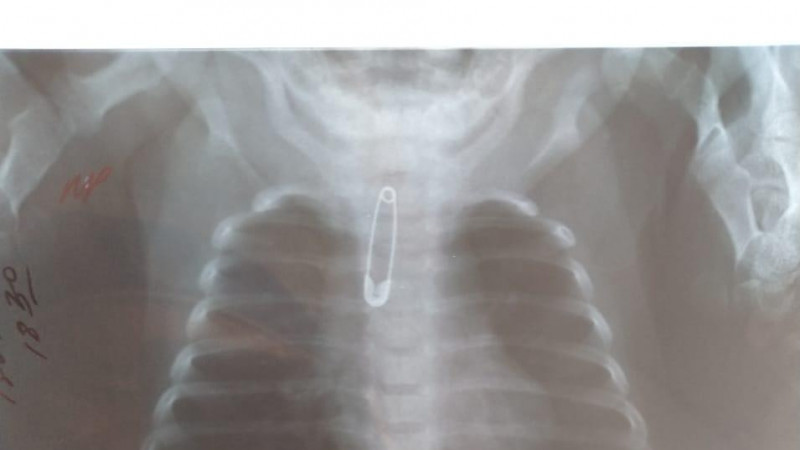

В Шымкенте врачи спасли малышку, в горле которой застряла булавка

- 16 Апреля 2021